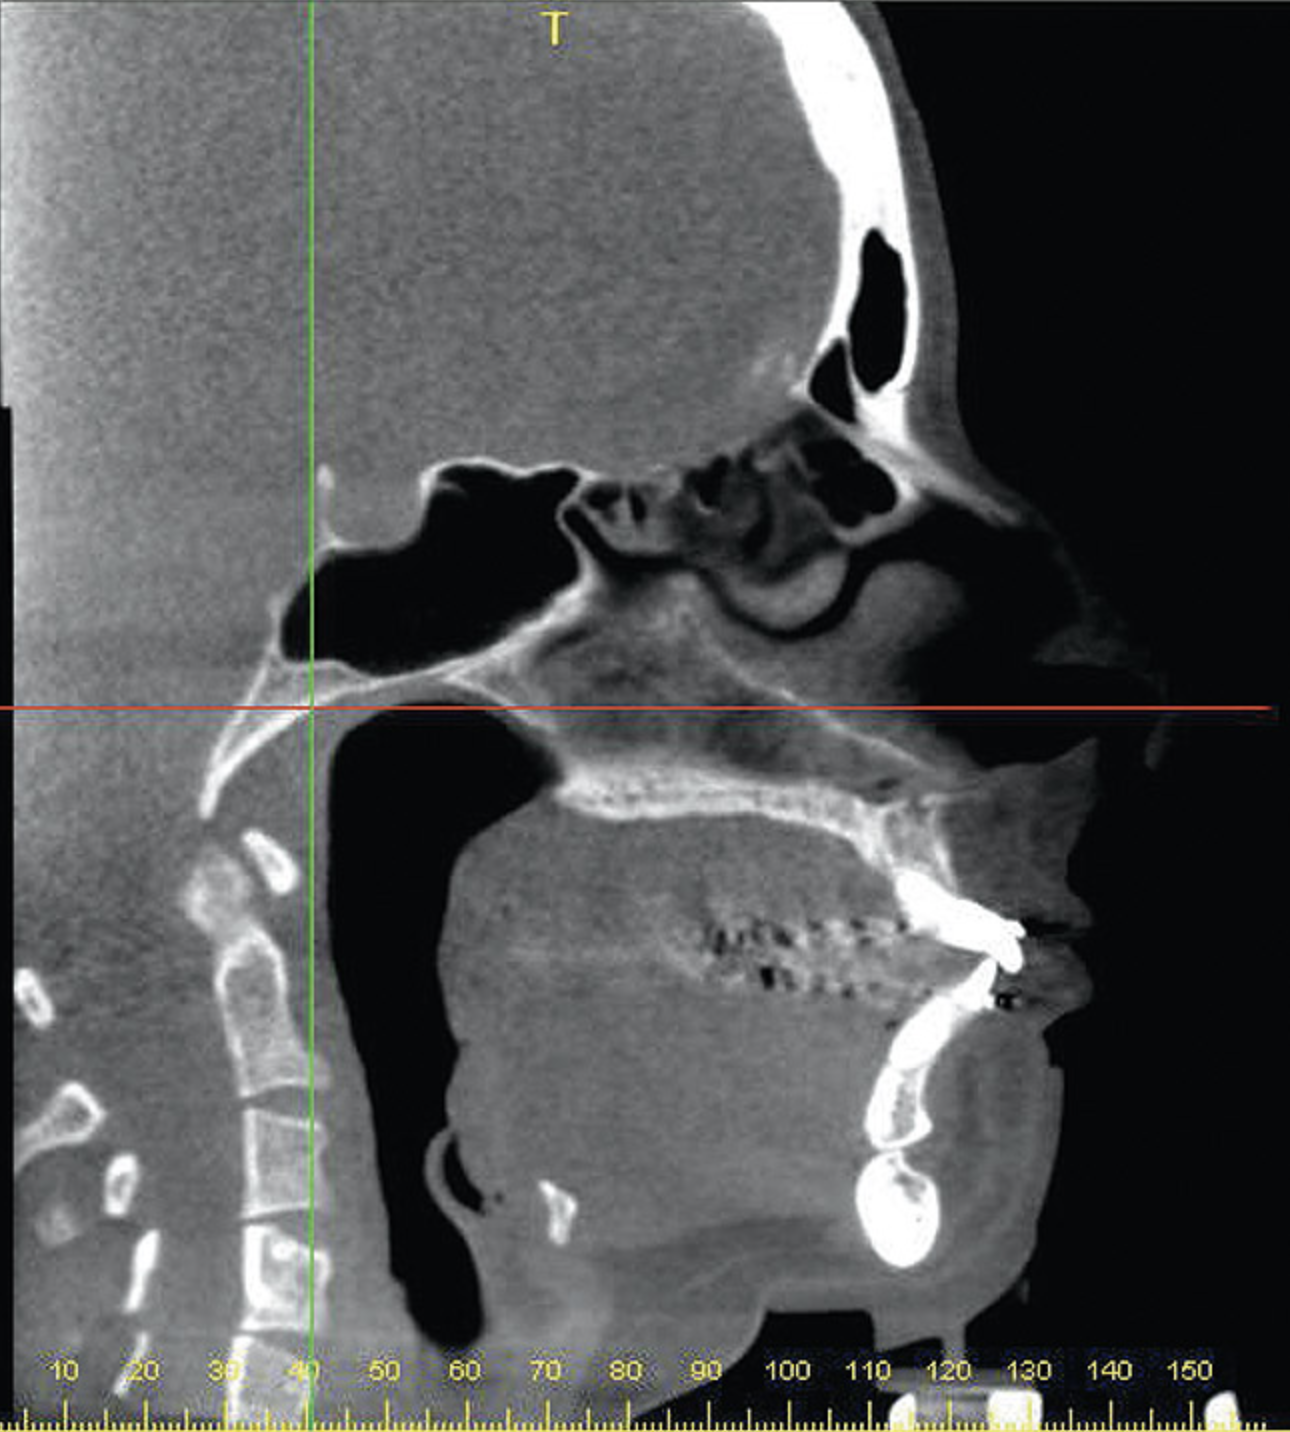

Figure 4A  Coronal section of 3D tomograph revealing axial alignment of posterior teeth. A) Dental alignment does not allow occlusal forces to be directed down long axis of teeth. Maxillary teeth had been tipped to the buccal to compensate for the transverse discrepancy. B) Teeth are positioned to allow occlusal forces to be directed down long axis of teeth.

Figure 4A

Figure 4B  Coronal section of 3D tomograph revealing axial alignment of posterior teeth. A) Dental alignment does not allow occlusal forces to be directed down long axis of teeth. Maxillary teeth had been tipped to the buccal to compensate for the transverse discrepancy. B) Teeth are positioned to allow occlusal forces to be directed down long axis of teeth.

Figure 4B